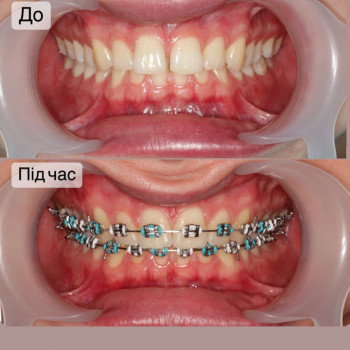

| Ортодонтия | |

| Установка брекетов | |

| Металлические брекеты | |

Якщо ти хочеш рівні зуби та красиву посмішку - тобі саме до нас!

Ми зробимо це на високому рівні!

А як саме наважитись на постановку брекетів?

Перший крок - це консультація ортодонта, Ви зможете дізнатись відповіді на запитання які Вас хвилюють. Перед постановкою брекетів усі зубки мають бути здорові, якщо ми бачимо карієс, його потрібно полікувати. Також потрібно зробити рентгенівські знимки для діагностики. За цей час, коли ми готуємо зуби до постановки брекетів, Ви зможете налаштуватись морально, звикнути з думкою що Ваша посмішка засяє новими барвами. На сьогоднішній час носіння брекетів являється престижним!